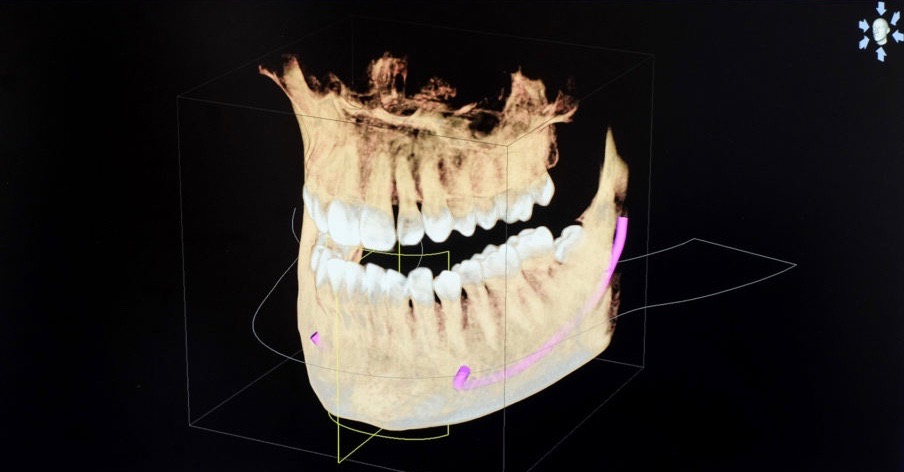

Bei der digitalen Volumentomographie (DVT) handelt es sich um ein neuartiges bildgebendes Verfahren, welches im Mund-Kiefer-Gesichtsbereich bei der Darstellung der Hartgewebe (u.a. Knochen) vergleichbare dreidimensionale Bilder liefert wie die konventionelle Computertomographie (CT).

Zum Tragen kommen die Vorteile der dreidimensionalen Bildgebung speziell im Bereich der Behandlungsplanung vor operativen Eingriffen. Hier bietet es dem Behandler die Möglichkeit, die Dreidimensionalität der knöchernen Verhältnisse eben auch in allen drei Dimensionen darzustellen und zu befunden. Somit steht, im Vergleich zum zweidimensionalen Röntgen, eine wesentlich genauere Befundung der Ausgangssituation und daraus resultierend auch eine genauere, weil vorhersehbare, OP-Planung zur Verfügung.